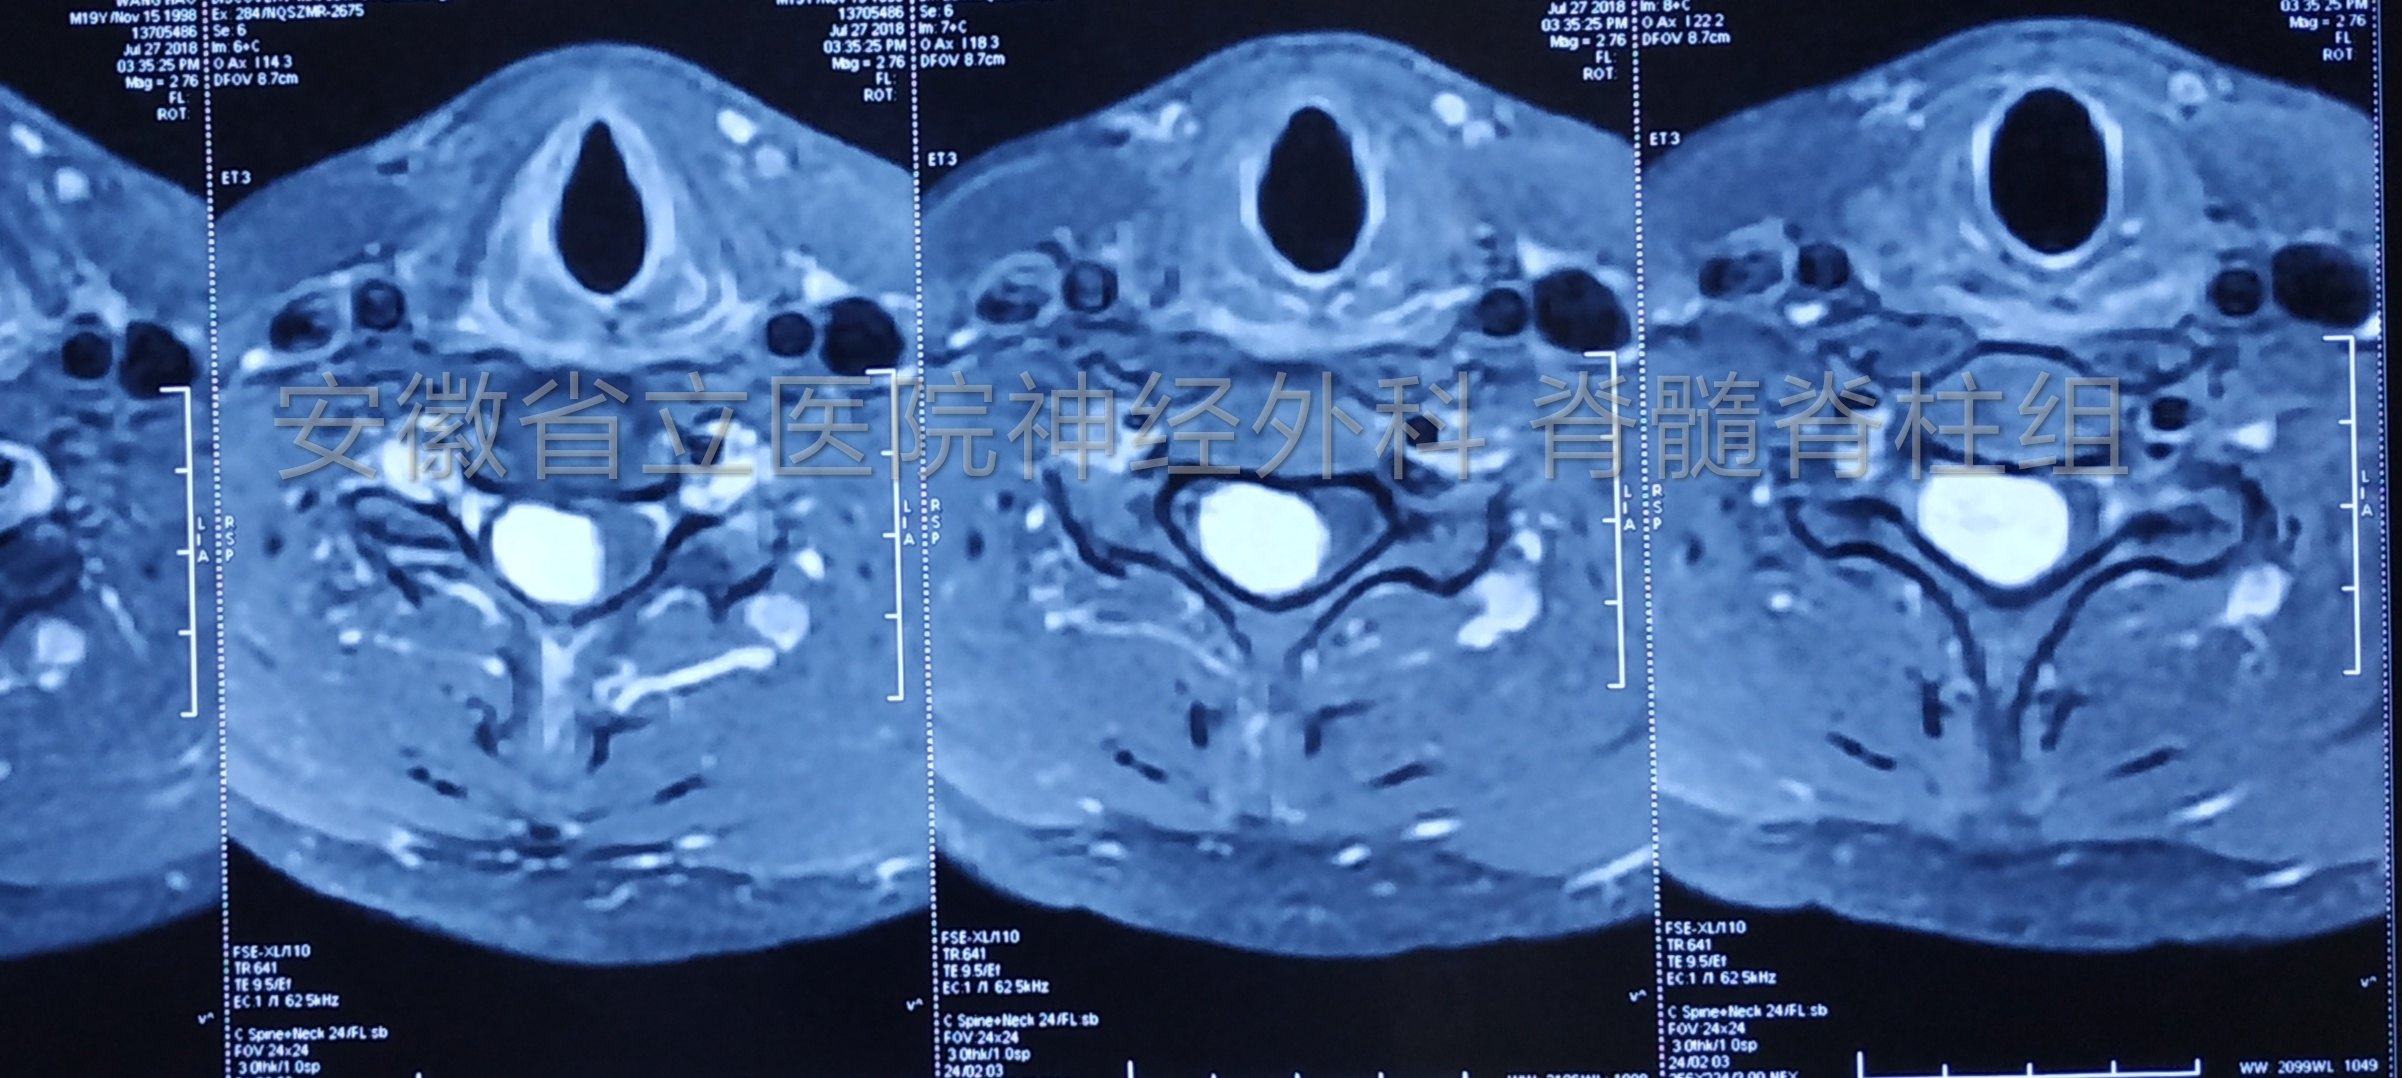

患者17岁,右侧肢体乏力1年入院,查体右侧上肢肌力4级弱,肌肉萎缩。磁共振显示颈椎管占位,完善检查后行手术切除。

手术中全程电生理监测,保护脊髓神经功能完整。

肿瘤切除后予以椎板骨质复位,术后复查显示椎管内肿瘤全切除,骨质复位良好,手术部位解剖完整,患者恢复快,脊柱稳定性得以保证。